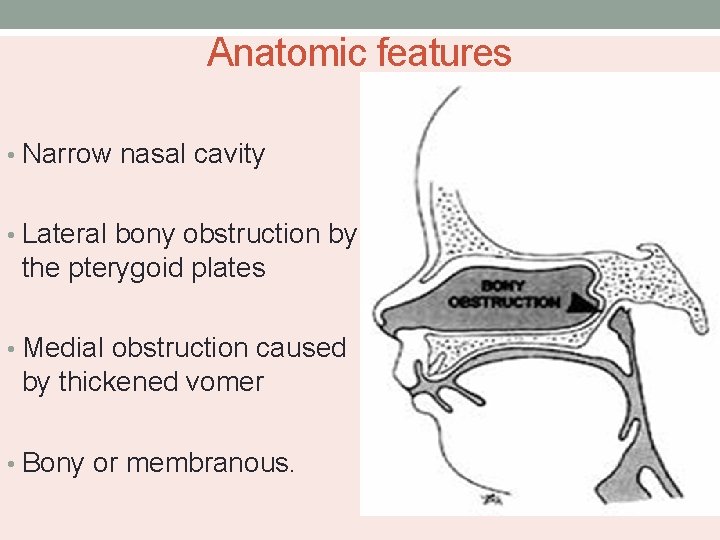

Anatomic features • Narrow nasal cavity • Lateral bony obstruction by the pterygoid plates • Medial obstruction caused by thickened vomer • Bony or membranous.